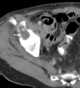

In medicine, wasting, also known as wasting syndrome, refers to the process by which a debilitating disease causes muscle and fat tissue to "waste" away. Wasting is sometimes referred to as "acute malnutrition" because it is believed that episodes of wasting have a short duration, in contrast to stunting, which is regarded as chronic malnutrition. [Source: Wikipedia ]